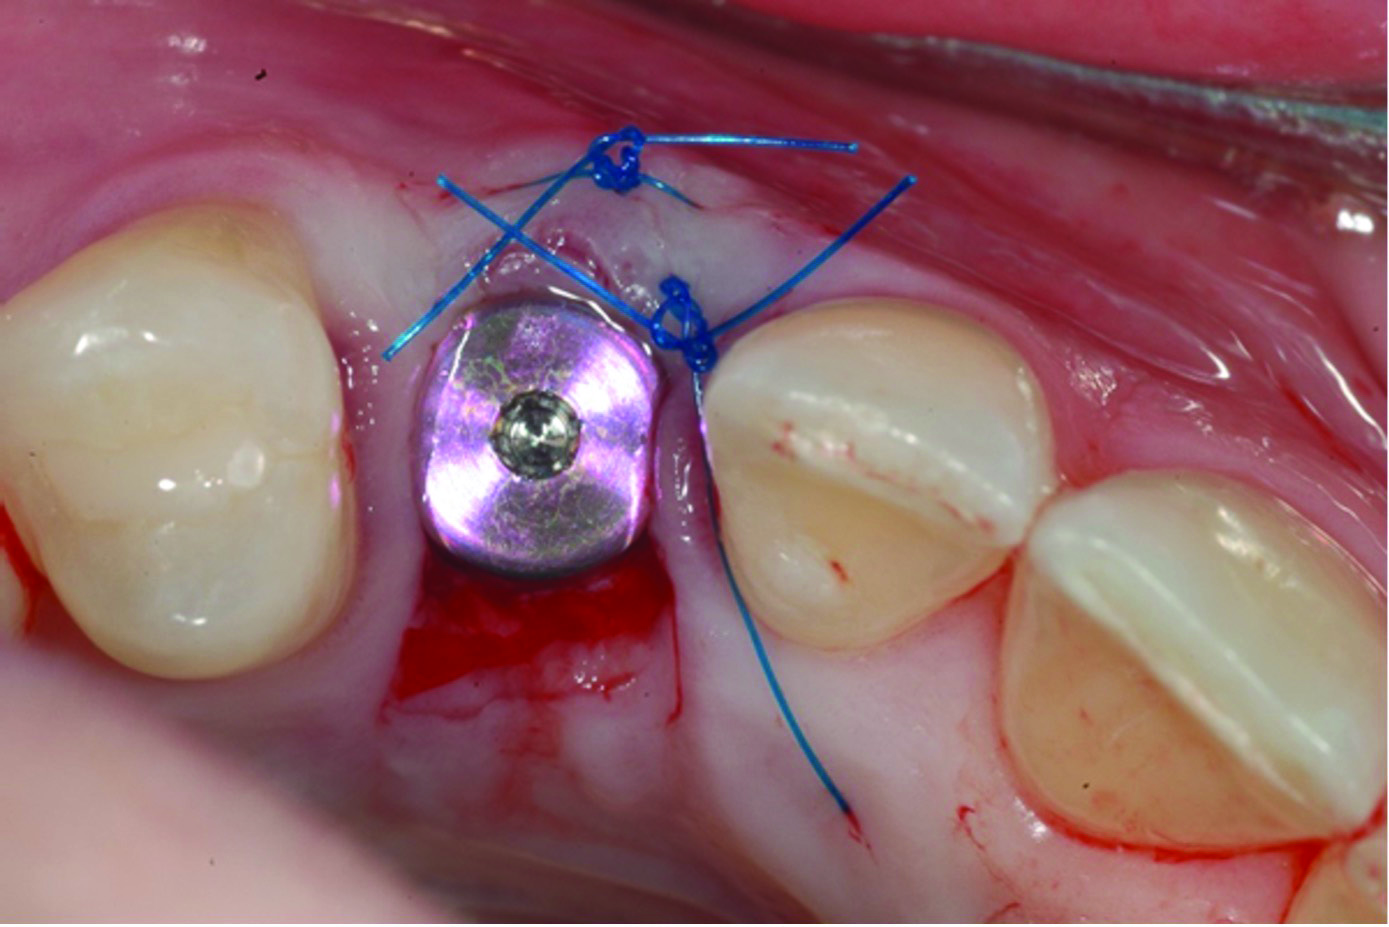

Fig 12 through Fig 14. Example of increasing MT with a roll technique. Fig 12: incision design for implant placement with a healing abutment placement and to enhance MT; the recipient site is prepared on the buccal side; the palatal aspect of the flap will be rolled to the buccal recipient site; Fig 13: insertion of roll of tissue taken from the palatal aspect of the flap; Fig 14: implant placement with healing abutment.